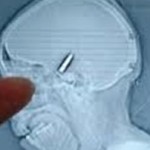

Με μια σφαίρα 22 χιλιοστών καρφωμένη στο κεφάλι του ζούσε για πέντε ολόκληρα χρόνια ένας Πολωνός, χωρίς καμία επίδραση στην υγεία του.

Η σφαίρα βρέθηκε όταν ο 35χρονος επισκέφτηκε ένα γιατρό για να αφαιρέσει αυτό που ο ίδιος θεωρούσε ότι είναι κύστη.

Όταν οι γιατροί του έδειξαν τη σφαίρα, εκείνος θυμήθηκε ότι τον είχαν χτυπήσει στο κεφάλι σε ένα πάρτι, μεσάνυχτα παραμονής πρωτοχρονιάς «το 2004 ή το 2005», αλλά το είχε ξεχάσει γιατί ήταν «πολύ μεθυσμένος», όπως είπε εκπρόσωπος της Αστυνομίας.